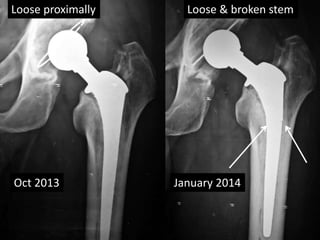

Observations - THR

• In THR stem brake due to fixed distal part and

loose proximal part.

• Since proximal part is loose, it needs revision.

• In contrast to THR, breakage of AMP stem is

due to loose distal part and a Fixed proximal

part.

Feb 2012

Oct 2013 January 2014

Loose proximally Loose & broken stem

Well fixed stem Loose stem

Broken stem